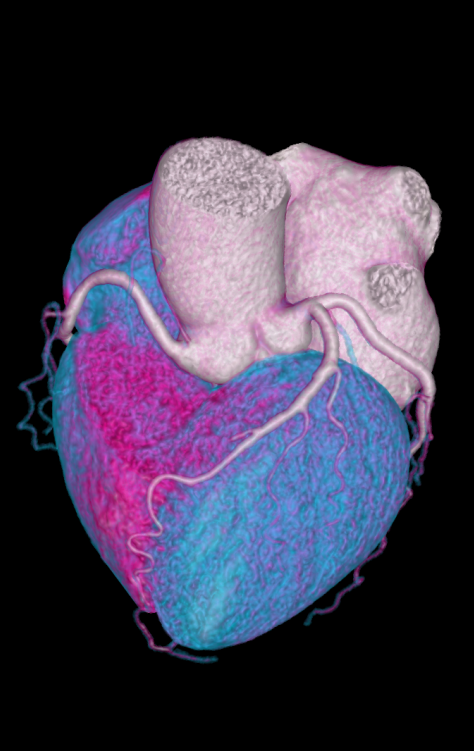

无限制心脏成像

天河640的宽体探测器单圈扫描即可覆盖全心脏,搭配业内最快机架转速和独家AI冠脉追焦技术,可实现单心动周期内无限心率的冠脉成像,不管是对于严重心律不齐、房颤、房扑,还是超高心率等一般CT做不了的心脏检查的情况,天河640都能在单心动周期内获得优质图像。在获得优异图像质量的同时,较常规CT降低了70%-90%的辐射剂量。

图片说明:高心率(90次/分钟)冠状动脉CTA,成像质量同样优秀。